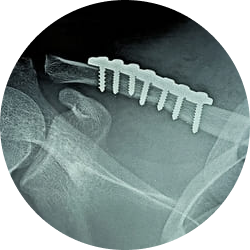

Данная разновидность одномоментного хирургического вмешательства совершается через хирургический доступ. Так, во время процедуры хирург под общим наркозом в условиях операционной делает разрез тканей, совмещает костные фрагменты аппаратами или руками, фиксирует их металлическими конструкциями: пластины, винты, спицы. По завершении операции конечность фиксируется шиной.

- Во время открытой репозиции специалист видит костные фрагменты в ране, возвращает их в физиологичное положение, фиксирует с помощью металлических спиц, пластин, штифтов и иных приспособлений.